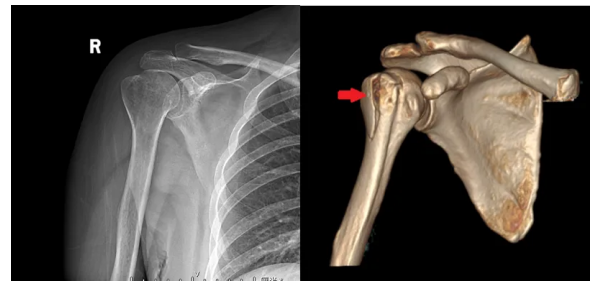

上图为右肩关节外伤患者,左图为普通X线片,右图为三维CT容积成像。

X线片仅见右肱骨大结节骨质密度减低,难以判断是否有骨折;而三维CT容积成像,可以清晰显示右肱骨大结节的骨折及骨片分离情况。